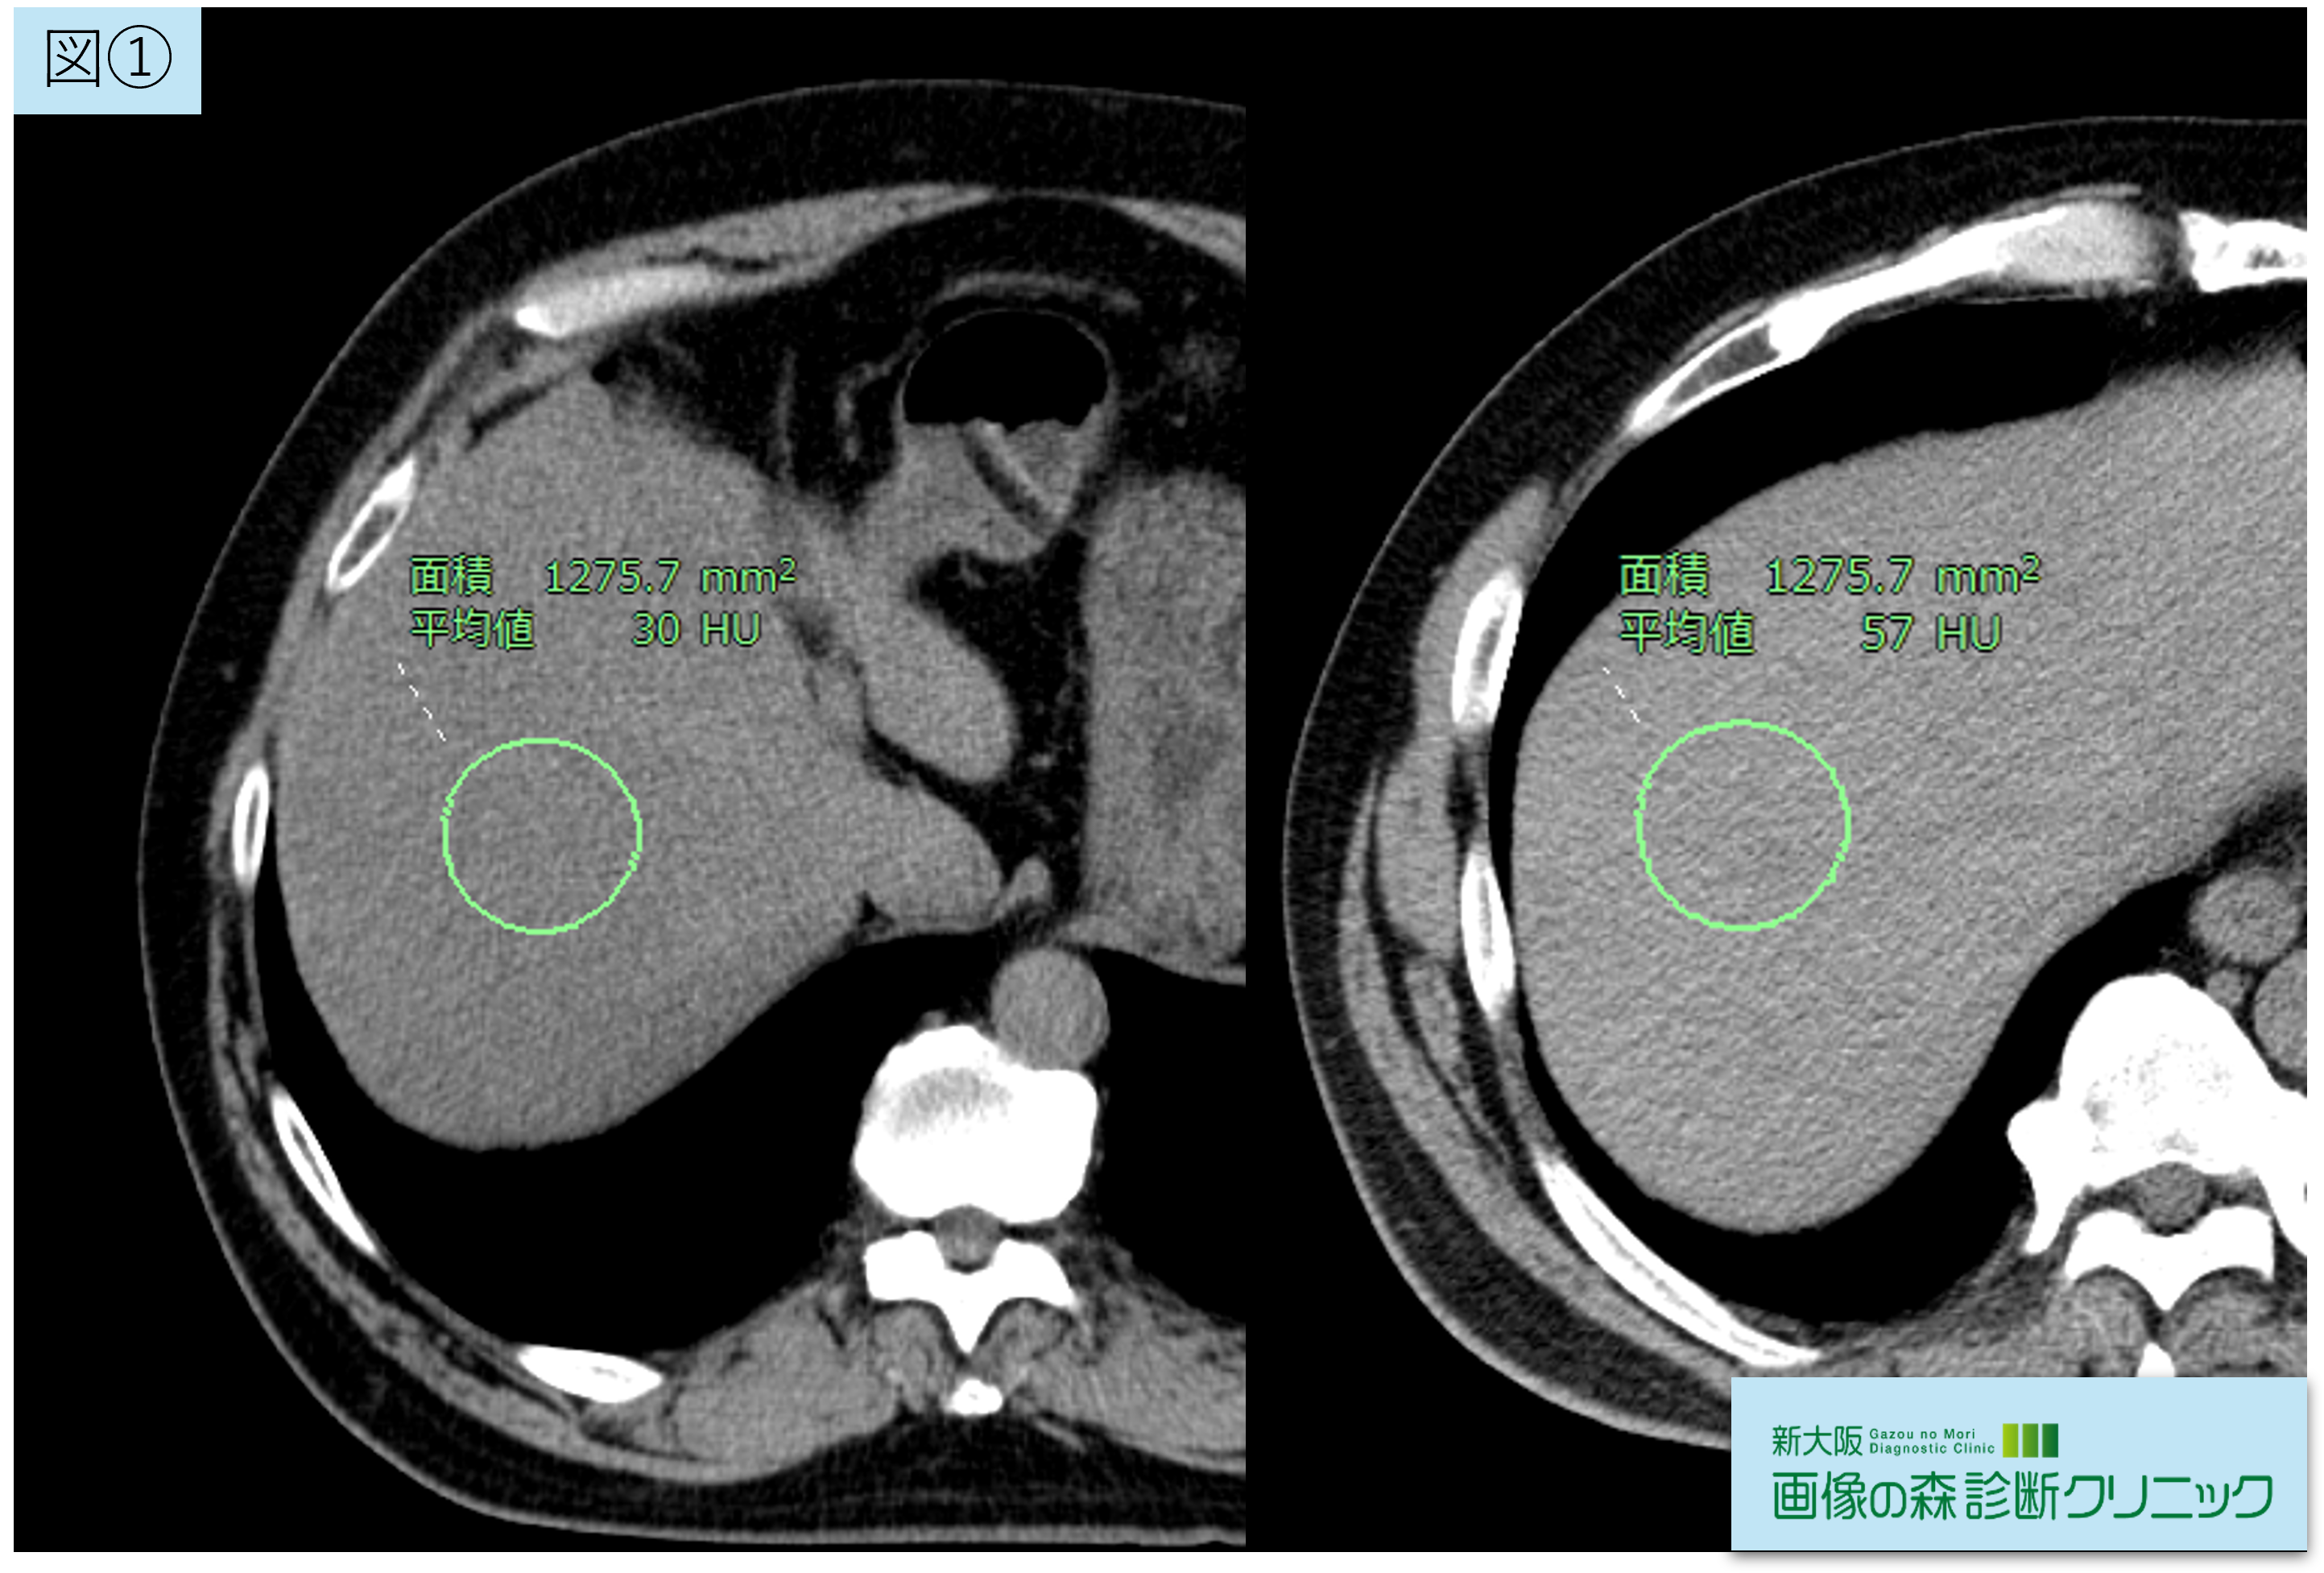

図①は脂肪肝と診断がついた時の画像(左)と、

その1年後に脂肪肝の改善があった画像(右)です。

画像内の〇で囲われた範囲はCT値を測定しています。

肝臓のCT値が40HU以下または、肝脾比が0.9以下の場合に脂肪肝の可能性が高く、

採血データと合わせて診断がつきます。